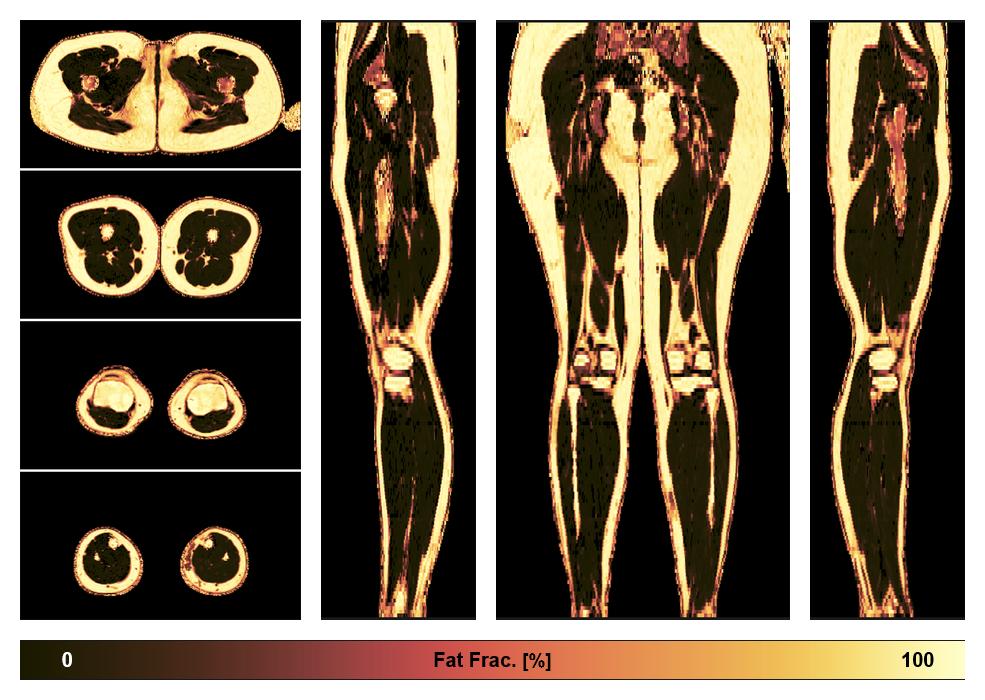

• Fat fraction

The fat fraction of the lower extremity obtained from the dixon reconstruction for muscle water fat quantification.